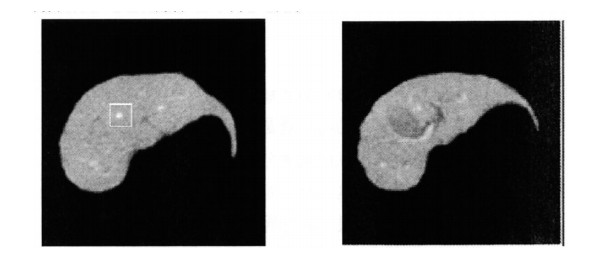

Figure 4.  Schematic diagrams of the internal liver tube

Figure 8.  Three-dimensional reconstruction of hepatic veins

Figure 9.  Three-dimensional smoothing effect diagrams